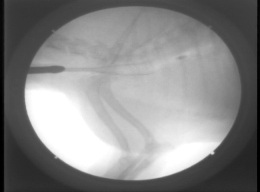

処置:自作シリコンステント(図5)、Wallstentに交換、さらに前方に1本追加(図6)。

図6 症例1の第371病日。ステント前方再虚脱し、同サイズのWallstentを前方に1本追加。

図7 症例1の第475病日。気管支鏡検査所見。ステント前端および内部に反応性肉芽形成。

図8 症例1の第538病日。2週間ごとにマイトマイシンCを肉芽部分に塗布し、肉芽消失。

図9 症例1の第1010病日。アルゴンプラズマ凝固(APC)およびマイトマイシンC(MMC)塗布したが、4ヵ月たつと肉芽再発。

図10 図9と同日、内視鏡で診断後、ただちにAPCおよびMMC塗布し、ただちに気道開存を得た。